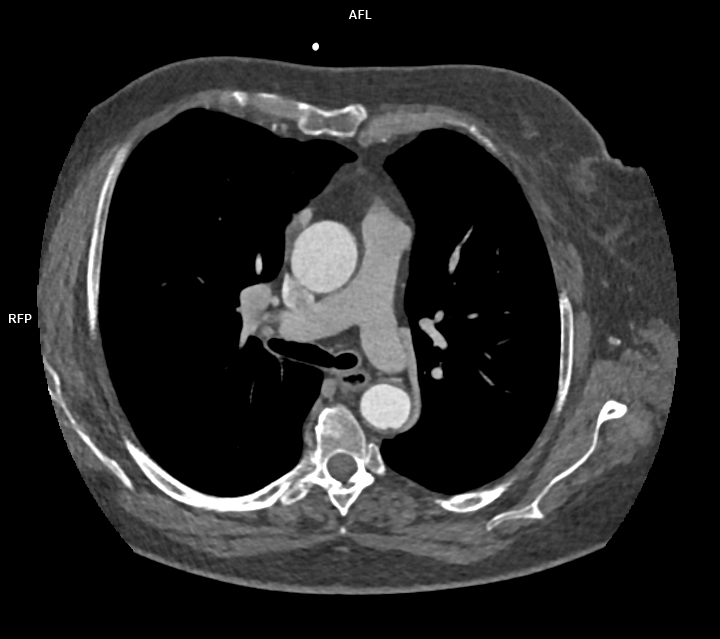

Figura 1: reconstrucție axială din achiziție CT postcontrast

Discuţie caz nr 47: variantă anatomică de formare a sistemului venos cav inferior cu persistența de venă cavă superioară stângă – există varinate anatomice în care vena cavă superioară stânga este singurul element de drenaj al sângelui de la nivelul extremității cefalice și membrelor superioare. Este important de cunoscut la pacienții ce urmează proceduri interventionale / de cateterizare cardiacă sau la pacienții care au nevoie de cateter venos central.